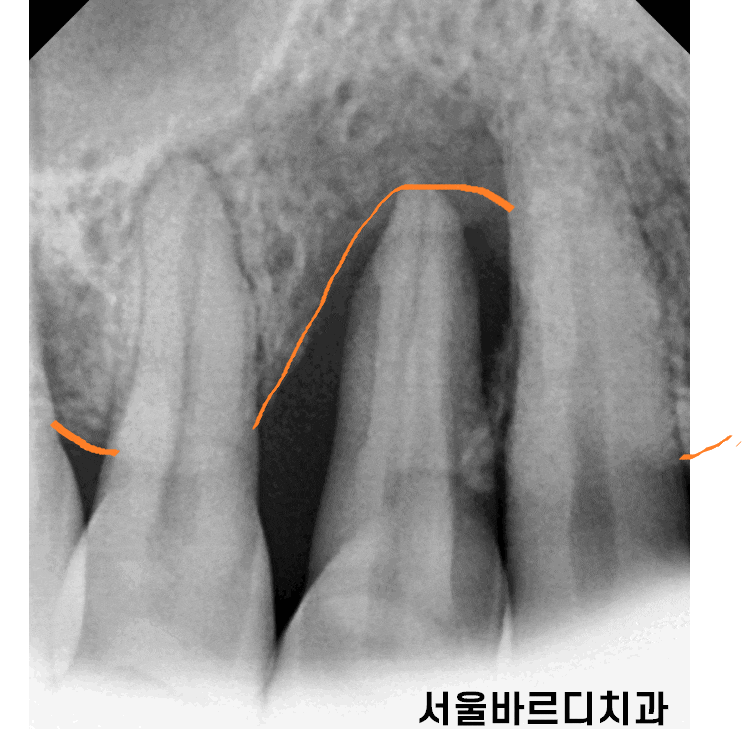

240712 대표적인 잇몸 뼈 녹음

대표적으로 치주 질환이 있습니다.

잇몸에 염증이 생기고

염증이기에 잇몸 뼈를 녹이는거죠~

초기에는 간단한 스케일링만으로도 해결이 되지만

잇몸 뼈 녹음이 한번 발생하면 절대 돌아오지 않습니다.

계속적인 관리를 통해 더 이상 녹지 않게 해주는 것 뿐이죠~